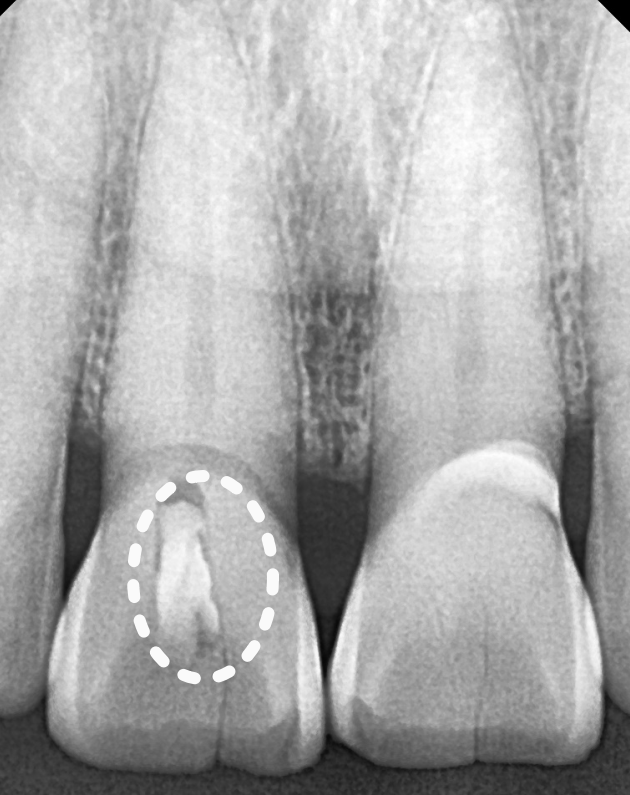

치아를 살펴보니 앞니 앞면 중앙에 금이 쭉 가 있었습니다.

치경부(치아와 잇몸 경계) 쪽엔 마모가 진행되어 뿌리 쪽이 파여있습니다.

250626 앞니 금 갔을 때, 방치하면 안 되는 진짜 이유 <파절 치료 사례>

특히 금이 더 깊게 간 오른쪽 앞니 통증을 호소하셨습니다.

250626

금이 간 부위가 너무 깊은 탓인지,

결국 신경까지 감염이 퍼져버려

통증이 사라지지 않았습니다.

안타깝지만, 신경치료를 진행해야 했습니다.

문제는 금이 간 부위가 상당히

크고 깊어서, 신경치료 중 치아가 깨질 위험이

커 보였다는 점입니다.